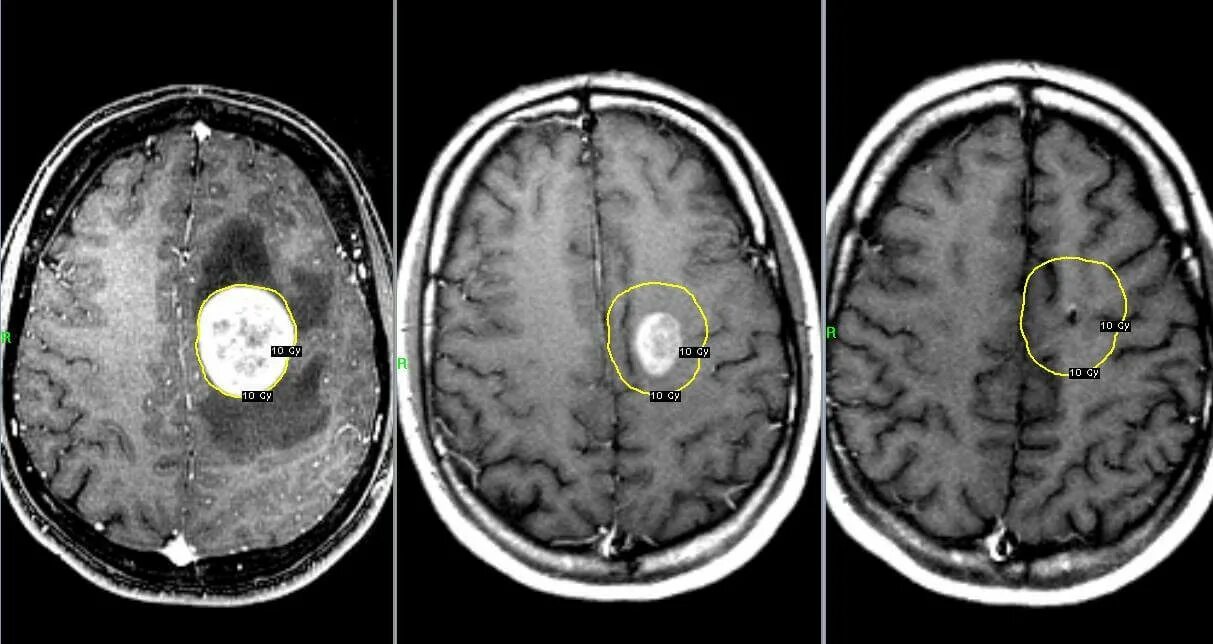

Отек головного мозга мрт